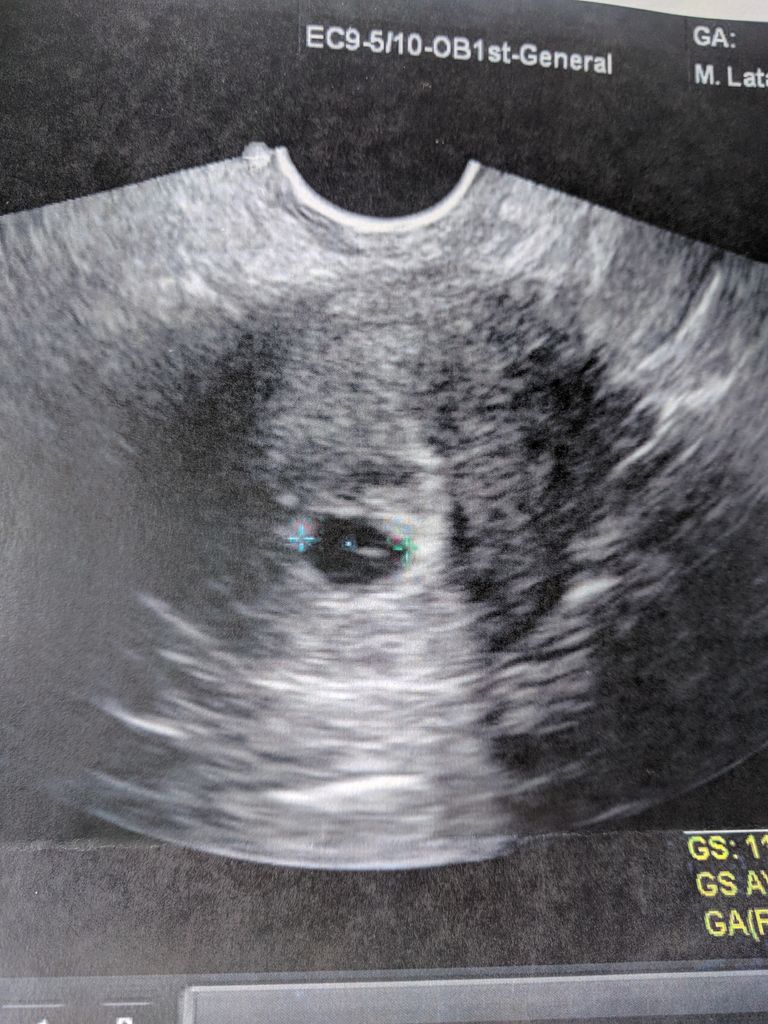

After 2 years of treatment, i finally got a bfp last tuesday, i am currently 5 weeks and 3 days pregnant. I went to the er, they did several test including blood work, an ultrasound, and a transvaginal ultra. I have been cramping a little and i just noticed that i am spotting ( slightly bleeding).